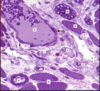

What tissue is this (yellow arrow)?

Smooth muscle

Compared to other muscle types, smooth muscle is ______________ & ______________.

non-striated and involuntary

The contractile proteins in smooth muscle are ____________ & ____________.

Actin and myosin